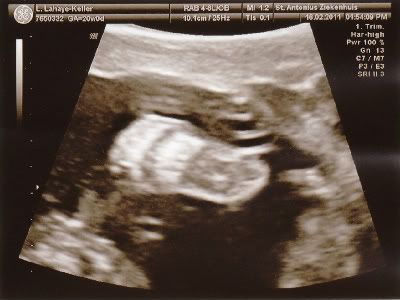

We hebben vandaag de 20 weken echo gehad en alles is in orde met de kleine!

Moet nog wel een keer terug volgende week, want ze kon niet alles goed zien maar de belangrijkste dingen waren helemaal in orde! Ben echt opgelucht... Hieronder wat echo foto's.